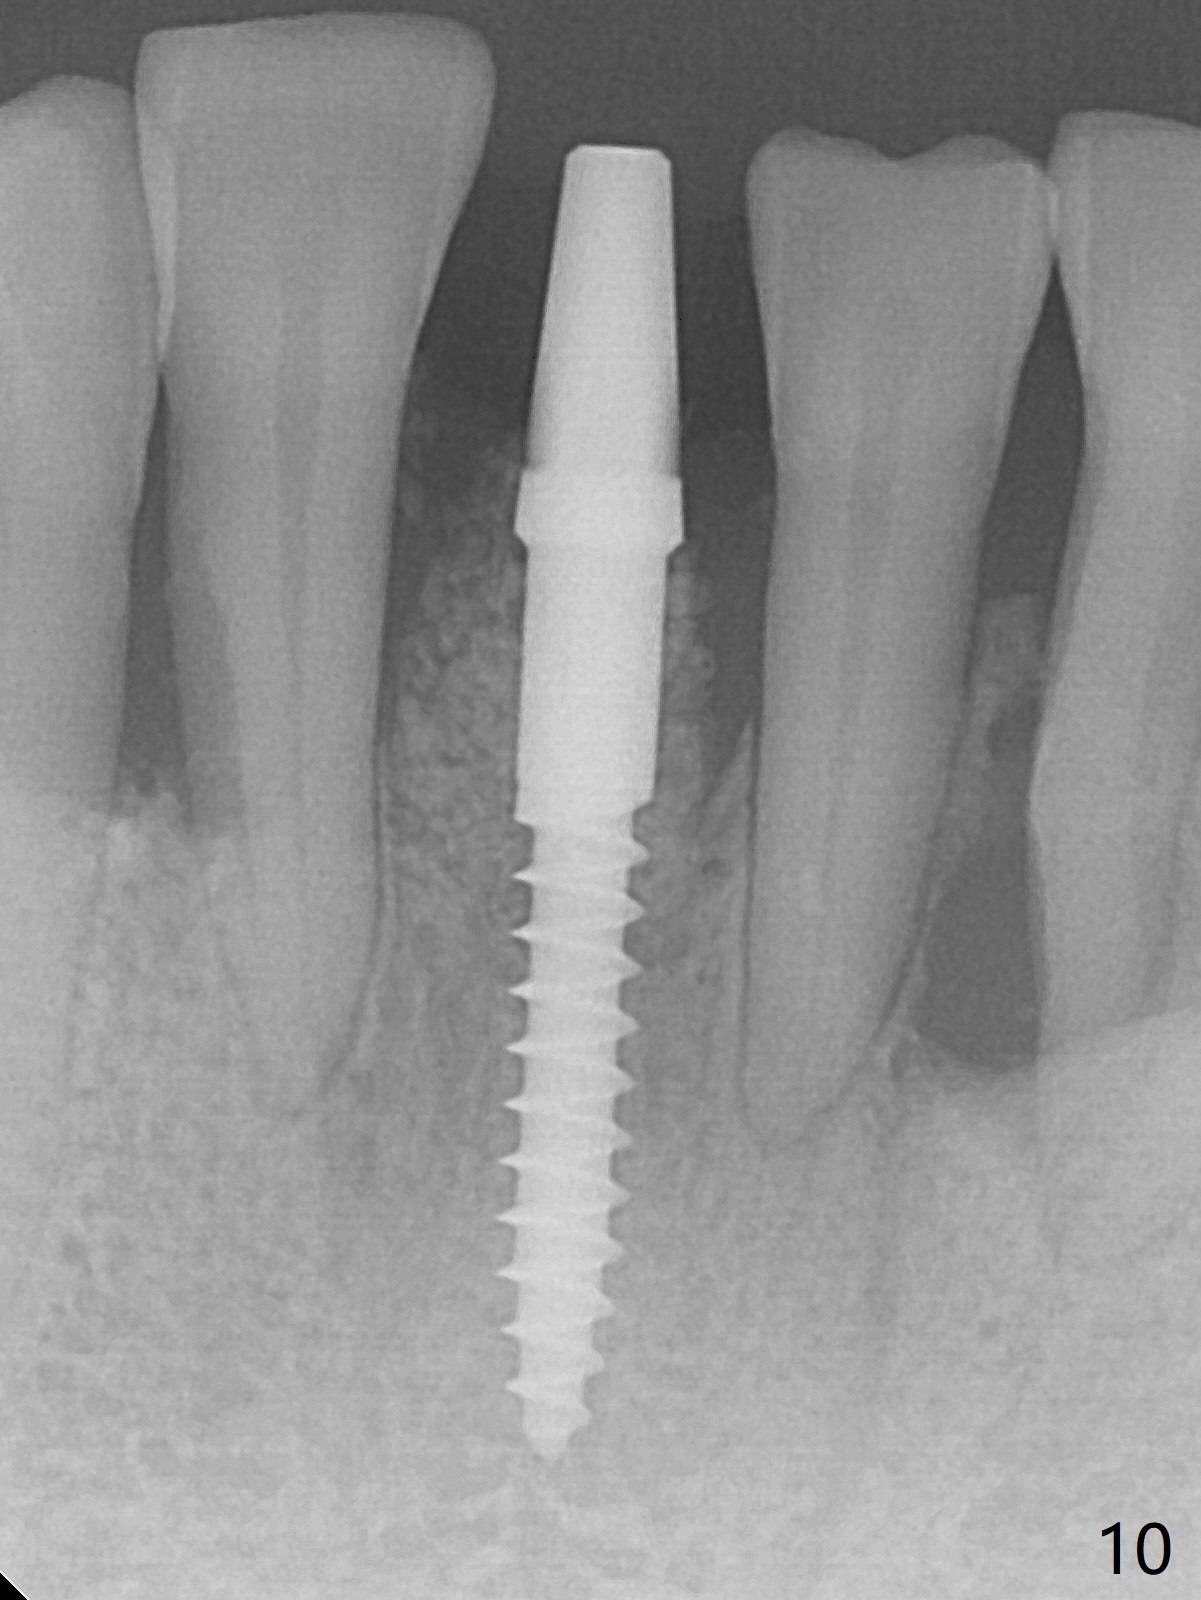

There is gingival inflammation at #25 buccally (Fig.1) and lingually (Fig.2). The bone loss is severe (Fig.3). Soft and hard tissue heights are 5 mm (cuff will be 4 mm) and 10 mm (implant will be 12 mm with 2 mm outside the native bone, Fig.4). The apex of the affected tooth appears deviated distal (Fig.5 *). The initial osteotomy happens to follow the long axis of the socket (Fig.6); to establish a correct trajectory, a new osteotomy should be made at the site labeled as a red line. In fact it is executed as planned (Fig.7). Because of the narrow flat ridge buccolingually, a 2.5x12(4) mm 1-piece implant is placed with >40 Ncm (Fig.8). With deeper placement of the implant, Vanilla graft is placed in 2 steps (Fig.9,10). The patient will return 2.5 months for extraction and implant of the fused teeth #22 and 23. No implant threads are exposed 10 months postop (Fig.11). CT taken 11 months postop shows that the 2.5 mm implant is in the middle of the bone (Fig.12) or 2 years post cementation (Fig.13).